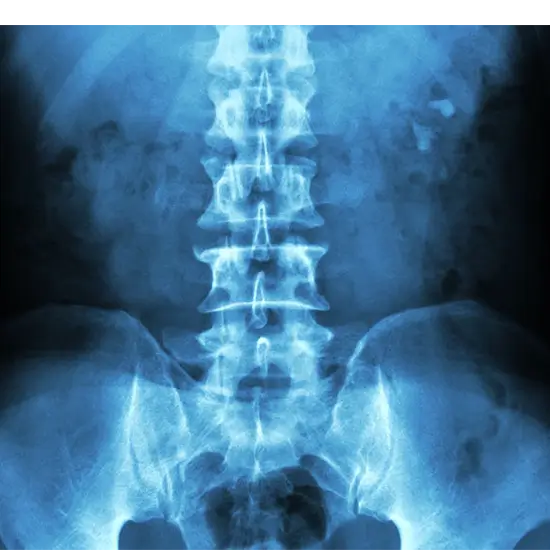

X-Ray Abdomen - Test, Procedure & Cost

X-Ray Abdomen

An abdomen X-ray shows the stomach, intestines, gall bladder, base of the lungs, liver, and spleen. It is called a KUB X-ray when it is used to look at the kidney, ureter, and bladder.